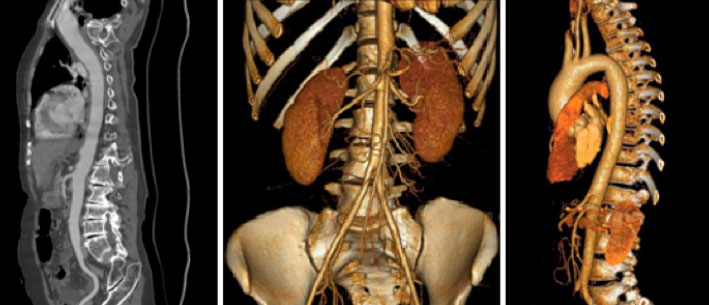

Tomografía computarizada Vascular o angioTC

< Volver a "Tomografía Computarizada (TC) con Inteligencia artificial"Está indicado para el estudio de la patología arterial, descartar aneurismas o malformaciones vasculares, e incluso para la planificación del tratamiento con stents, entre otras aplicaciones.